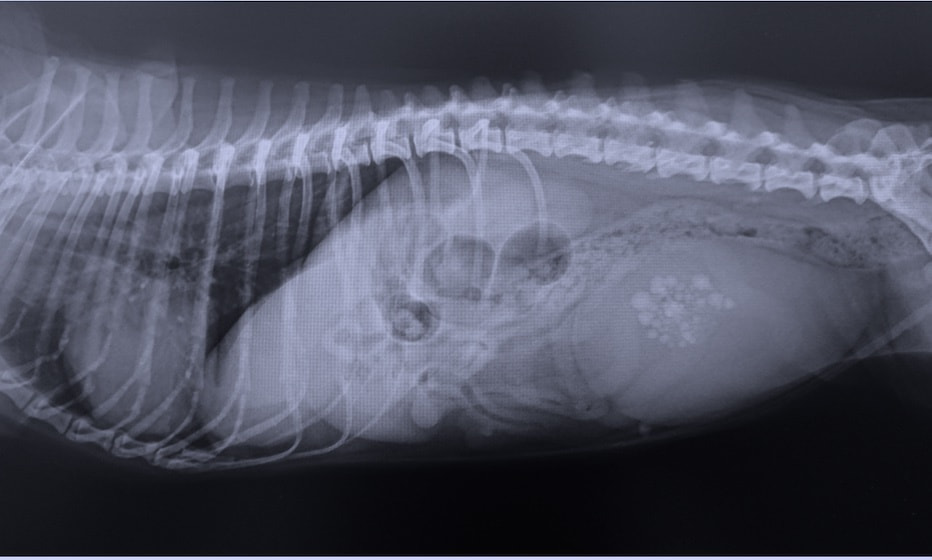

変形性脊椎症は、身体を支えている背骨(脊椎)が年齢とともに少しずつ変形してしまう病気です。多くは無症状なためレントゲン検査で偶然見つかることも珍しくありません。しかし、変形した脊椎が神経を圧迫することで痛みや歩行異常が現れることがあります。椎間板の変性や加齢による椎体間の不安定性が原因と考えられています。症状が見られる場合は、鎮痛剤で痛みを和らげたり、温熱療法などの理学療法で筋肉の緊張をほぐしながら経過を見ていきます。最近活動量が減ってきた、歩きにくそうにしている、などの変化は病気のサインかもしれません。なにか気になる症状があればお気軽にご相談下さい。